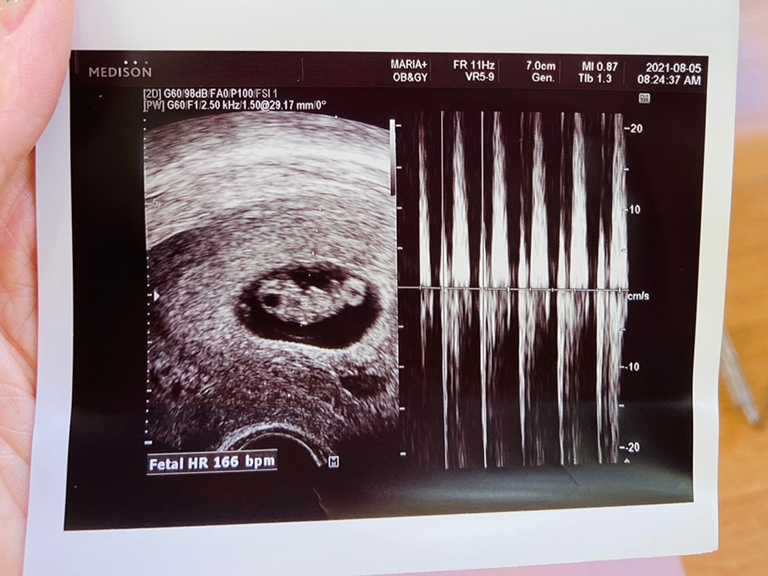

8주 3일째인 8월 5일. 송파 마리아플러스 진료가 있어서 다녀왔습니다 🙂

정재훈 원장님이 방학이라 이경희 과장님 진료 받았어요~5층은 처음 가봤는데 2층보다 좋더라고요 대기 공간도 더 넓고 되게 돼있고.. 진료실 안에.. 초음파 보는 모니터도 정면에 하나 더 있어서 편했어요!

따복이는… 머리 엉덩이 길이 1.91cm 심장 소리 166bpm으로 아주 잘 자랐어요.

다음 날… 8주 4일째 되는 날이었습니다서울 삼성병원 산부인과 진료를 다녀왔어.요~

오수영 선생님께 진료를 받았습니다.오수영 교수님이 너무 친절하고 설명도 잘한다고 권유해서 갔습니다. 너무 친절하고 설명도 잘하셨어요.:)

초음파를 봐 주시는 선생님도 친절하셔서 참 다행이라고 생각을 합니다.~~